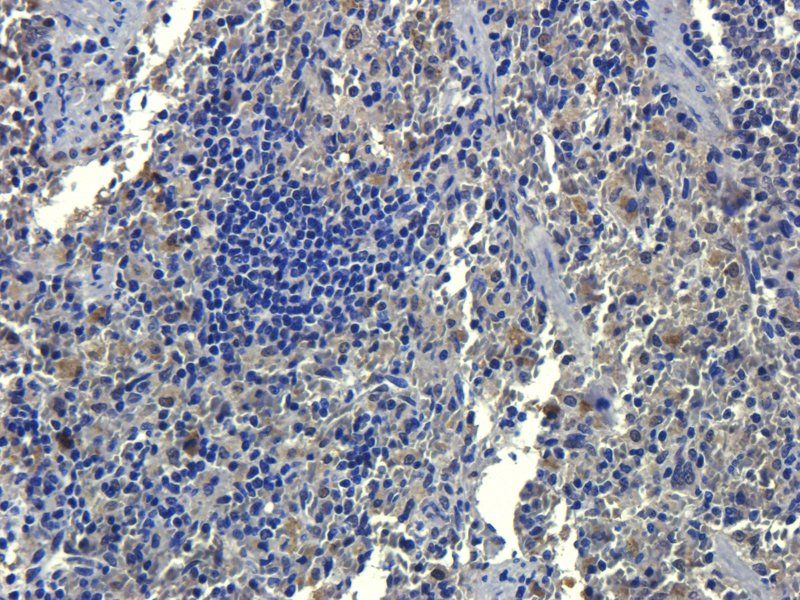

100 μg - OPG antibody [orb247239]Featured

ELISA, ICC, IF, IHC-P, WB

Bovine, Canine, Human, Mouse, Rat

Rabbit

Polyclonal

Unconjugated

100 μg